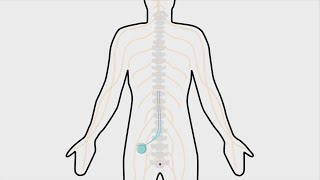

San Diegan scientists offer non-opioid relief to chronic pain sufferers

San Diegan scientists offer non-opioid relief to chronic pain sufferers